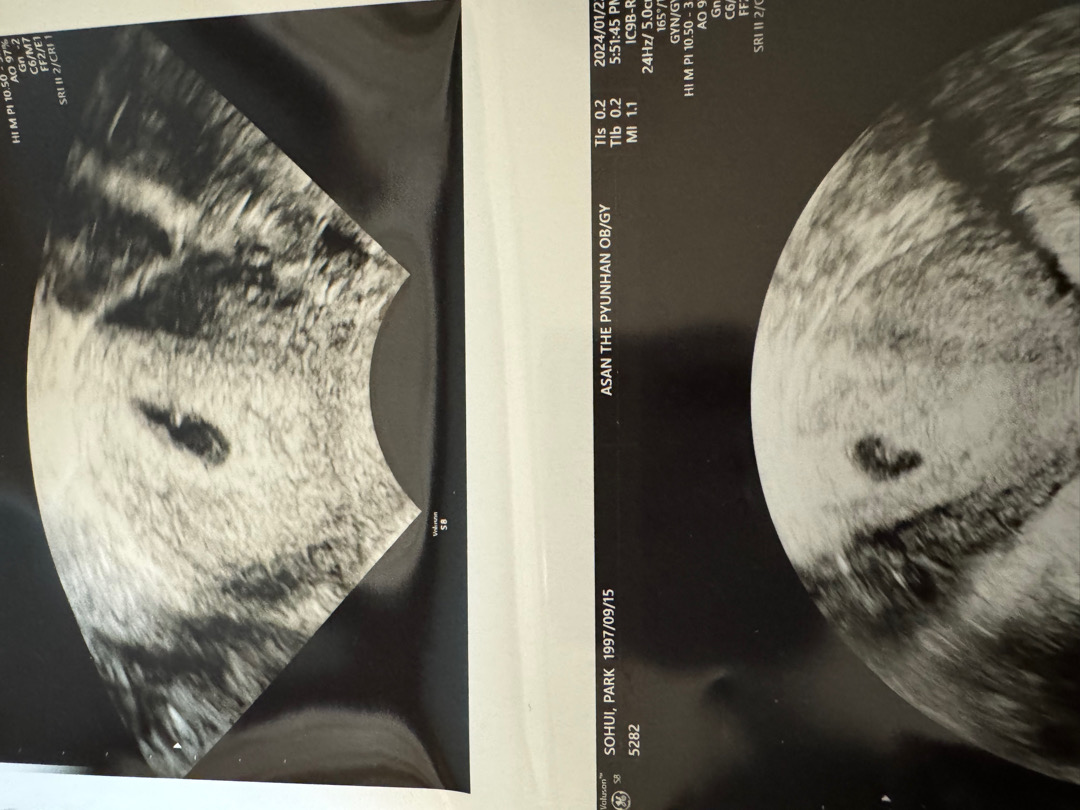

์๊ธฐ์ง์ปท๋ ํ์ธํ๋ฌ๊ฐ๋ค๊ฐ ์๊ฐ์น๋ ๋ชปํ๊ฒ 5์ฃผ0์ผ์ฐจ์ ๋ํฉ์ ๋ดฃ๋๋ฐ ์์๊ฐ์ด์ง๋ง๋น์ด์์ด๋ณด์ฌ์ ์ ์ฒ๋ผ ์ด๋ฐ๋ถ๋ ๊ณ์ ง๋ํด์์ฉ ๐๐ป ์์ฌ์ค์ ์๋ฆฌ์์ก์๊ตฌ ๋ํฉ๋๋ณด์ธ๋ค๊ณ ํ์ จ๊ธดํ๋๋ ๋ค๋ฅธ๋ถ๋ค์ ์ด์๊ฒ ๋ชจ์์ด๋ผ ๊ดํ ๊ถ๊ตผํด์์ฉ ๐ฅบ

์ ๋ 5์ฃผ 2์ผ์ฐจ์ ๋ณด๊ณ ์๋๋ฐ ๋ํฉ์ด ์ด์ ์กฐ๊ธ์ฉ ์๋ผ๋๊ฑฐ๊ฐ๋ค๊ณ ์ฃผ์์ ๋นํด ๋ฆ์ง๋ง ๋ฐฐ๋์ด ๋ฆ๊ฒ๋๊ฑฐ๊ฐ๋ค ํ์ จ์ด์ !!!